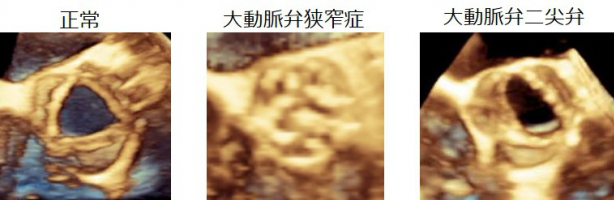

大動脈弁狭窄症は、弁口面積や通過血流速度などの精密な計測が必須です。最初に、経胸壁心エコー検査を行い重症度を判定します。

3Dエコーにより、手術中の解析から、適正なステントサイズ選択を検証したり、リアルタイムでの形態評価を行うことが可能です。